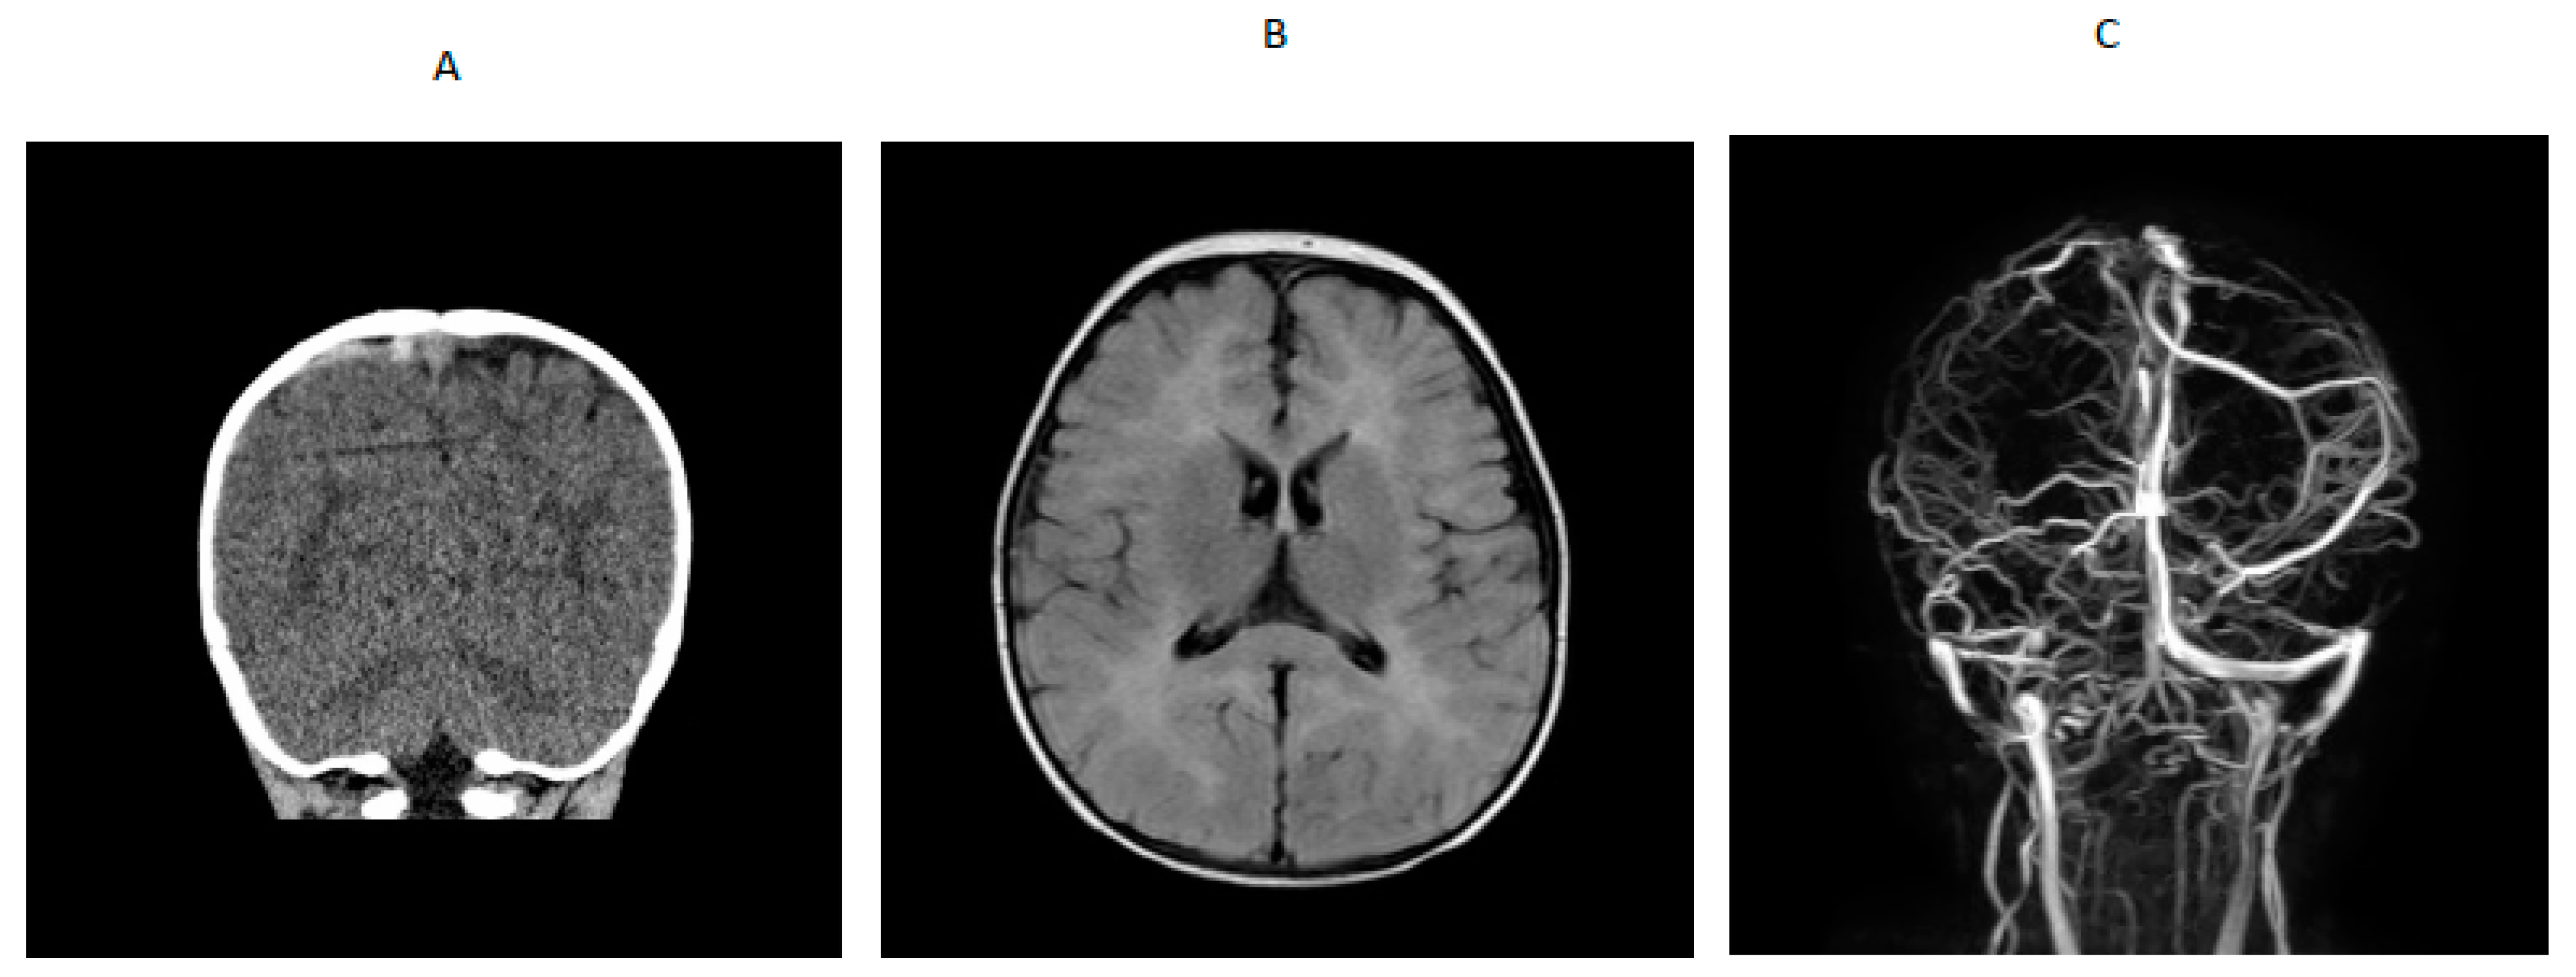

A 14-month-old boy presented to an outside hospital with loss of consciousness, peri-oral cyanosis and seizure-like activity. A computed tomography (CT) brain scan showed venous hyperdense enlarged cortical vein over the right parietal convexity extending into the superior sagittal sinus that was consistent with thrombosis. Upon transfer to a tertiary hospital, a brain MRI /MRV indicated cerebral venous thrombosis and abnormal T2 prolongation visualized diffusely throughout white matter of both cerebral hemispheres and involving the corpus callosum, anterior commissure and internal capsule, on T2-weighted images (Figure 1). An electroencephalogram (EEG) showed generalized slowing with no epileptiform activity. He was started on levetiracetam. Blood for hypercoagulable work-up showed elevated total homocysteine of 260.61 µmol/L (normal range was 6.6 to 14.8). Quantitative plasma amino acids showed elevated methionine (118 µmol/L; normal range is 14–50) with markedly elevated homocystine (45 µmol/L; normal range is 0–2) that was consistent with a diagnosis of cystathionine β-synthase deficiency. Homocystinuria gene panel testing showed a paternally inherited likely pathogenic variant (c.904G>A) and a maternally inherited pathogenic variant (c.667-14_667-7del(intronic)) in the CBS gene. Plasma very long chain fatty acids, lysosomal enzyme panel, plasma acylcarnitine profile, urine organic acids, serum methylmalonic acid, and ceroid neuronal lipofuscinosis enzymes, palmitoyl-protein thioesterase 1 (PPT1) and tripeptidyl peptidase 1 (TPP1) were normal. Factor V Leiden and prothrombin gene mutation, protein S and antithrombin levels and antiphospholipid antibody, β-2 glycoprotein and anti-cardiolipin antibody were normal. Protein C activity was decreased (67% with refence range of 80% to 160%), folic acid was low, serum vitamin B12 was low-normal (285 with reference range of 211 to 946 pg/mL), and serum carnitines were low. RBC folate was 29.2% (reference range was 30% to 42%). Lipoprotein lipase A level was normal (17 mg/dL with reference range of less than 29 mg/dL) and serum methylmalonic acid was 0.12 (normal is 0.0 to 0.4 µmol/L). After the diagnosis of homocystinuria was confirmed, he was placed on a low methionine diet, folic acid, vitamin B12, vitamin B6, betaine supplementation and enoxaparin. Serial brain MRI showed complete resolution of the cerebral venous thrombosis with improvement of the white matter changes in the brain, so enoxaparin was discontinued, and he was placed on daily 81 mg aspirin. The patient remained alert and stable throughout his hospitalization and did not show any neurological signs of any intracranial pathology after the initial seizure-like episode.

Figure 1.

(A) CT scan showing venous hyperdense cortical vein over right parietal convexity. (B) MRI showing extensive white matter changes. (C) MRV showing thrombosis of right parietal cortical vein extending into the superior sagittal sinus.